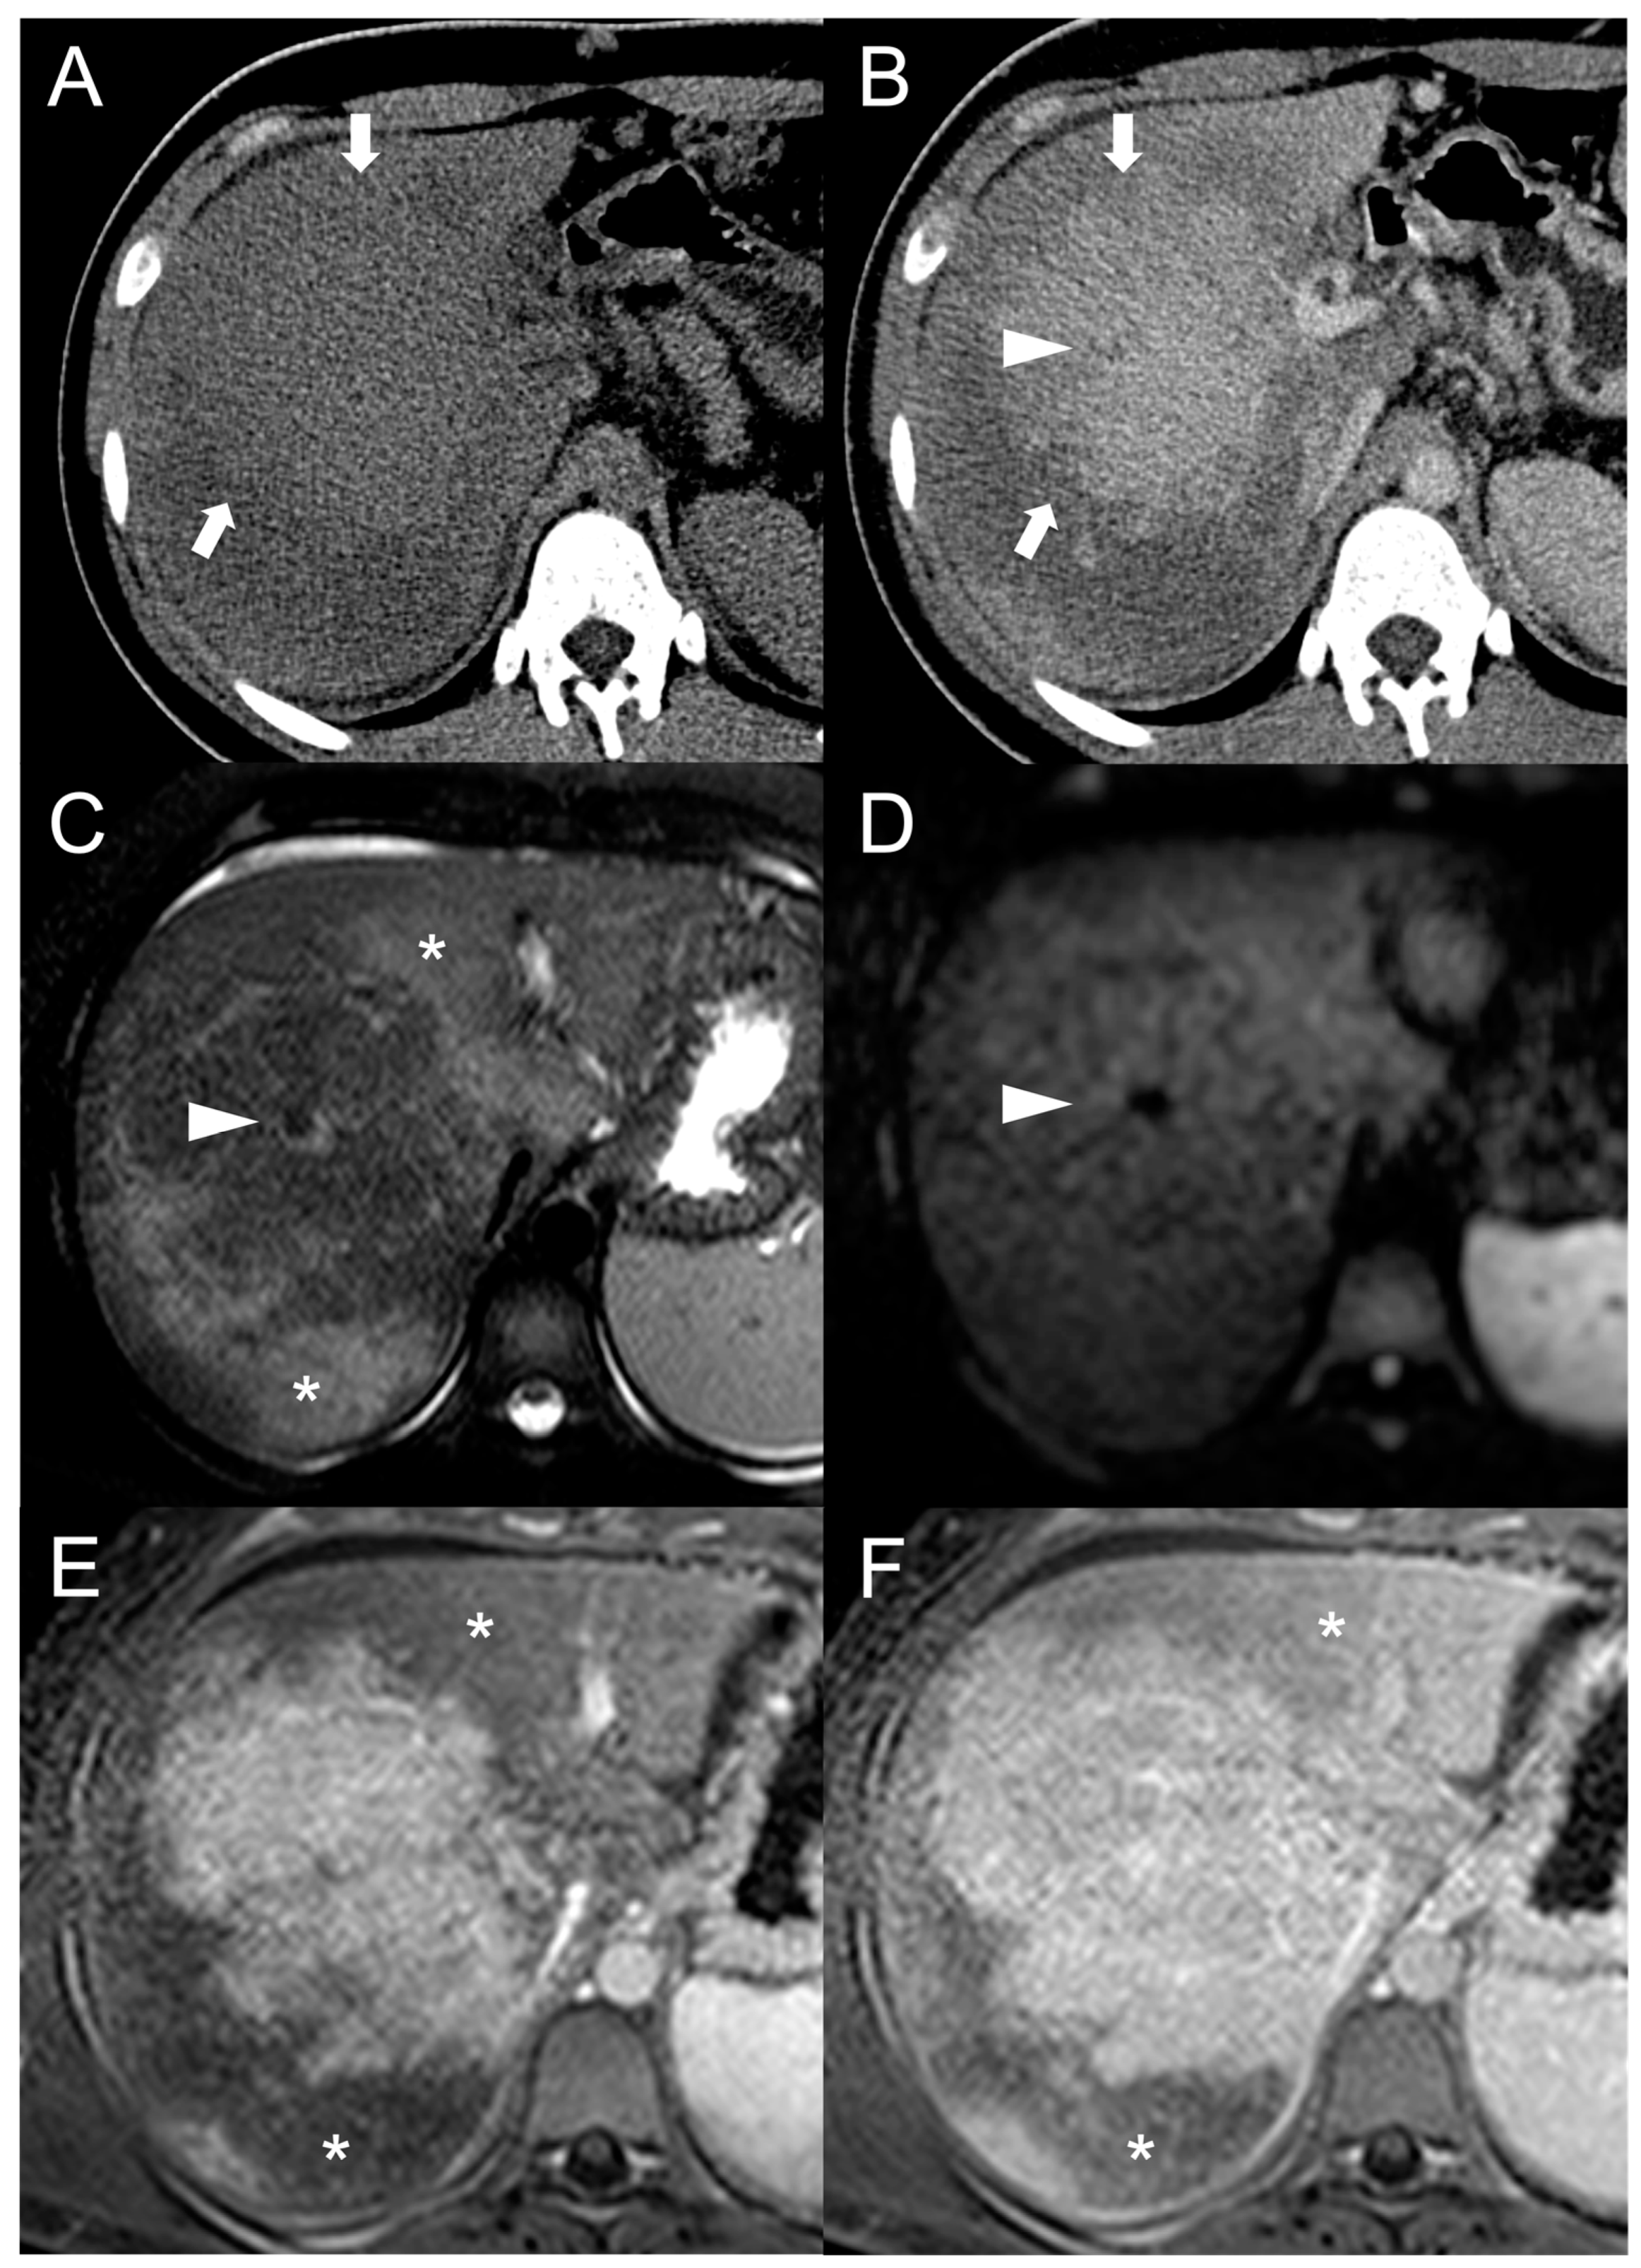

However, considering that approximately 25% of HCCs do not display washout in the portal and delayed phases, while up to one-third of FNH-like RNs can show it, the specificity of this feature for the diagnosis of HCC in BCS is relatively low. As reported by Van Wettere et al. [22], the association of homogeneous APHE and homogeneous washout was identified in one-third of benign lesions and in half of HCC cases. The resulting sensitivity and specificity for diagnosing HCC were 50% and 70%, respectively. When considering the combination of any type of APHE (homogeneous, peripheral or central) and any type of washout (homogeneous or peripheral), a sensitivity of 100% and a specificity of 61% were achieved. For this reason, given the risk of an unacceptable rate of false-positive results, the LI-RADS and AASLD/EASL criteria for the non-invasive diagnosis of HCC cannot be applied in BCS patients [28,29,30]. The differential diagnosis between FNH-like RNs and HCC becomes even more challenging due to the potential for the former to increase in size and/or in number. Therefore, it is important to consider additional features supportive of diagnosis of HCC, such as T1 hypointensity, hyperintensity in T2-weighted and high b-value DWI, and absence of a central scar on MRI [42], as shown in Figure 6.

Figure 6.

MRI examination of a 67-year-old female patient with Budd–Chiari syndrome reveals a new focal lesion of 13 mm in the left lobe (arrow). The lesion appears hyperintense on T2-weighted images (A), hypointense on T1-weighted images (B,D) and shows restricted diffusion in high-b-value DWI (C). After contrast agent administration, the lesion demonstrates marked enhancement on T1-weighted arterial phase images (E), followed by central washout with enhancing capsule on T1-weighted portal venous (F) and delayed (G) phases. On T1-weighted images in the hepatobiliary phase (H) the lesion shows a hypointense signal, suggesting a diagnosis of HCC. Perihepatic ascites (asterisks) can be observed on T2-weighted images (A) and DWI (C).

Hepatobiliary contrast agents provide valuable help in the differential diagnosis, as HCC most often demonstrates a hypointense signal in HBP. In the above-mentioned study [22], the combination of this feature with APHE and washout proved effective in distinguishing all HCC lesions from FNH-like RNs. Indeed, benign regenerative lesions typically appear isointense-to-hyperintense compared to the normal liver in HBP, regardless of the presence of washout on portal venous or delayed phase images.